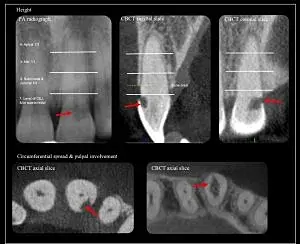

De esta manera, surge una clasificación que toma en cuenta el aspecto de la lesión en las imágenes tomográficas. Esta clasificación identifica tres elementos (7):

- Altura: se establece de acuerdo a la extensión vertical máxima de la lesión en la superficie radicular y en relación con la cresta ósea. La raíz es dividida, usando la unión amelocementaria y el ápice dentario como puntos de referencia, en tercios coronal, medio y apical. Para establecer la altura, se utilizan radiografías periapicales y los cortes sagital y coronal de la TCHC. Se divide en cuatro tipos:

- A nivel de la unión amelocementaria o coronal a la cresta ósea (supracrestal).

- Se extiende al tercio coronal de la raíz y apical a la cresta ósea.

- Se extiende al tercio medio de la raíz.

- Se extiende al tercio apical de la raíz.

- Extensión circunferencial: se clasifica de acuerdo a la máxima extensión dentro de la raíz. Se evalúa en el corte axial de la TCHC.

- A: menos o igual a 90°.

§ B: Entre 90° y 180°.

§ C: Entre 180° y 270°.

§ D: Más de 270°.

- Proximidad al conducto radicular: se evalúa en las vistas axiales de la TCHC.

- d: lesión limitada a dentina.

§ p: probable compromiso pulpar.

Estos tres aspectos juntos ofrecen información acerca del avance tridimensional de la lesión.

Figura 3. Ejemplo de clasificación tridimensional: altura, extensión circunferencial y proximidad al conducto radicular (Patel, 2018).